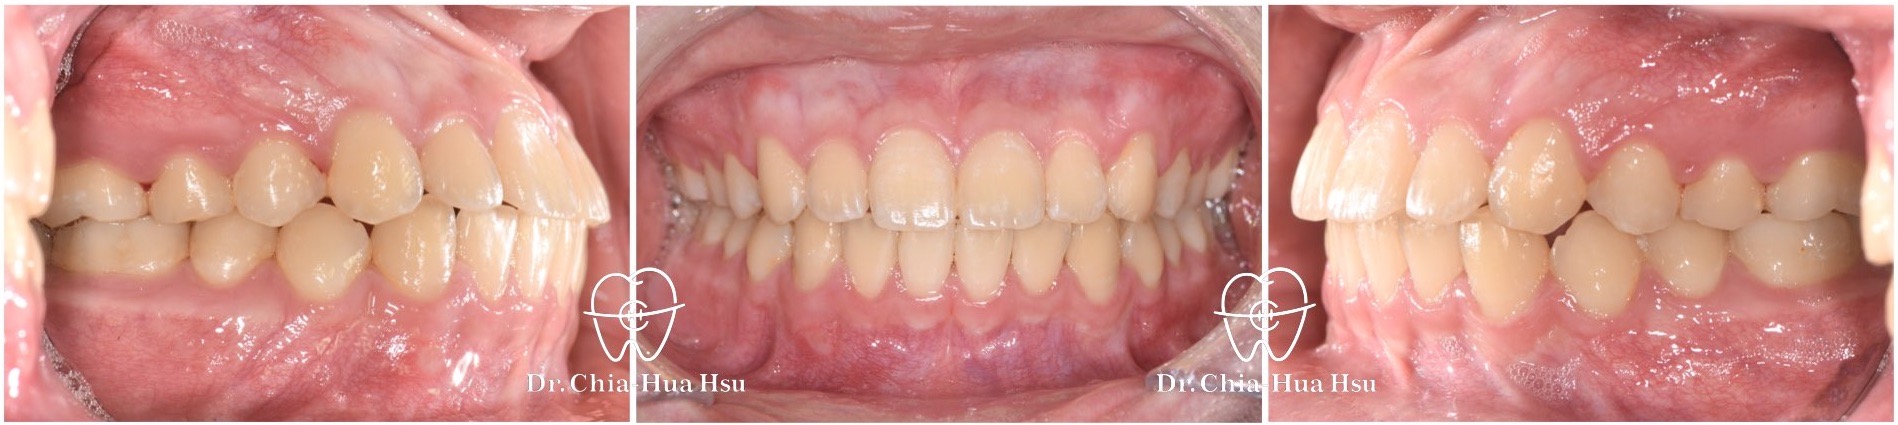

治療前

治療後